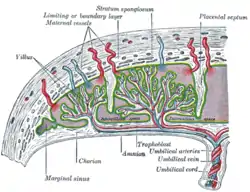

Scheme of placental circulation. | |

The umbilical arteries supply deoxygenated blood from the fetus to the placenta. Although this blood is typically referred to as deoxygenated, this blood is fetal systemic arterial blood and will have the same amount of oxygen and nutrients as blood distributed to the other fetal tissues. There are usually two umbilical arteries present together with one umbilical vein in the umbilical cord. The umbilical arteries surround the urinary bladder and then carry all the deoxygenated blood out of the fetus through the umbilical cord. Inside the placenta, the umbilical arteries connect with each other at a distance of approximately 5 mm from the cord insertion in what is called the Hyrtl anastomosis.[1] Subsequently, they branch into chorionic arteries or intraplacental fetal arteries.[2]